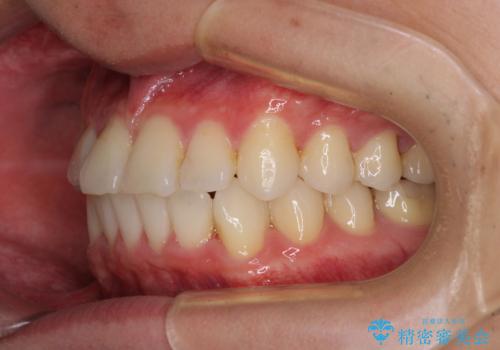

- 右下奥歯の虫歯がしみて痛いとのことで来院された患者様です。

神経近くにまで及ぶ大きな虫歯でしたが、速やかに処置を行い、痛みは即日解消されました。

虫歯が大きかったため、クラウンによる補綴治療が必要になる旨をお伝えしたところ、矯正治療にも興味があるとのことでした。

短期間で手間のかからない方法がご希望でしたので、ワイヤー装置による矯正治療を行うこととし、矯正治療後に右奥2歯をセラミッククラウンにて補綴することとしました。